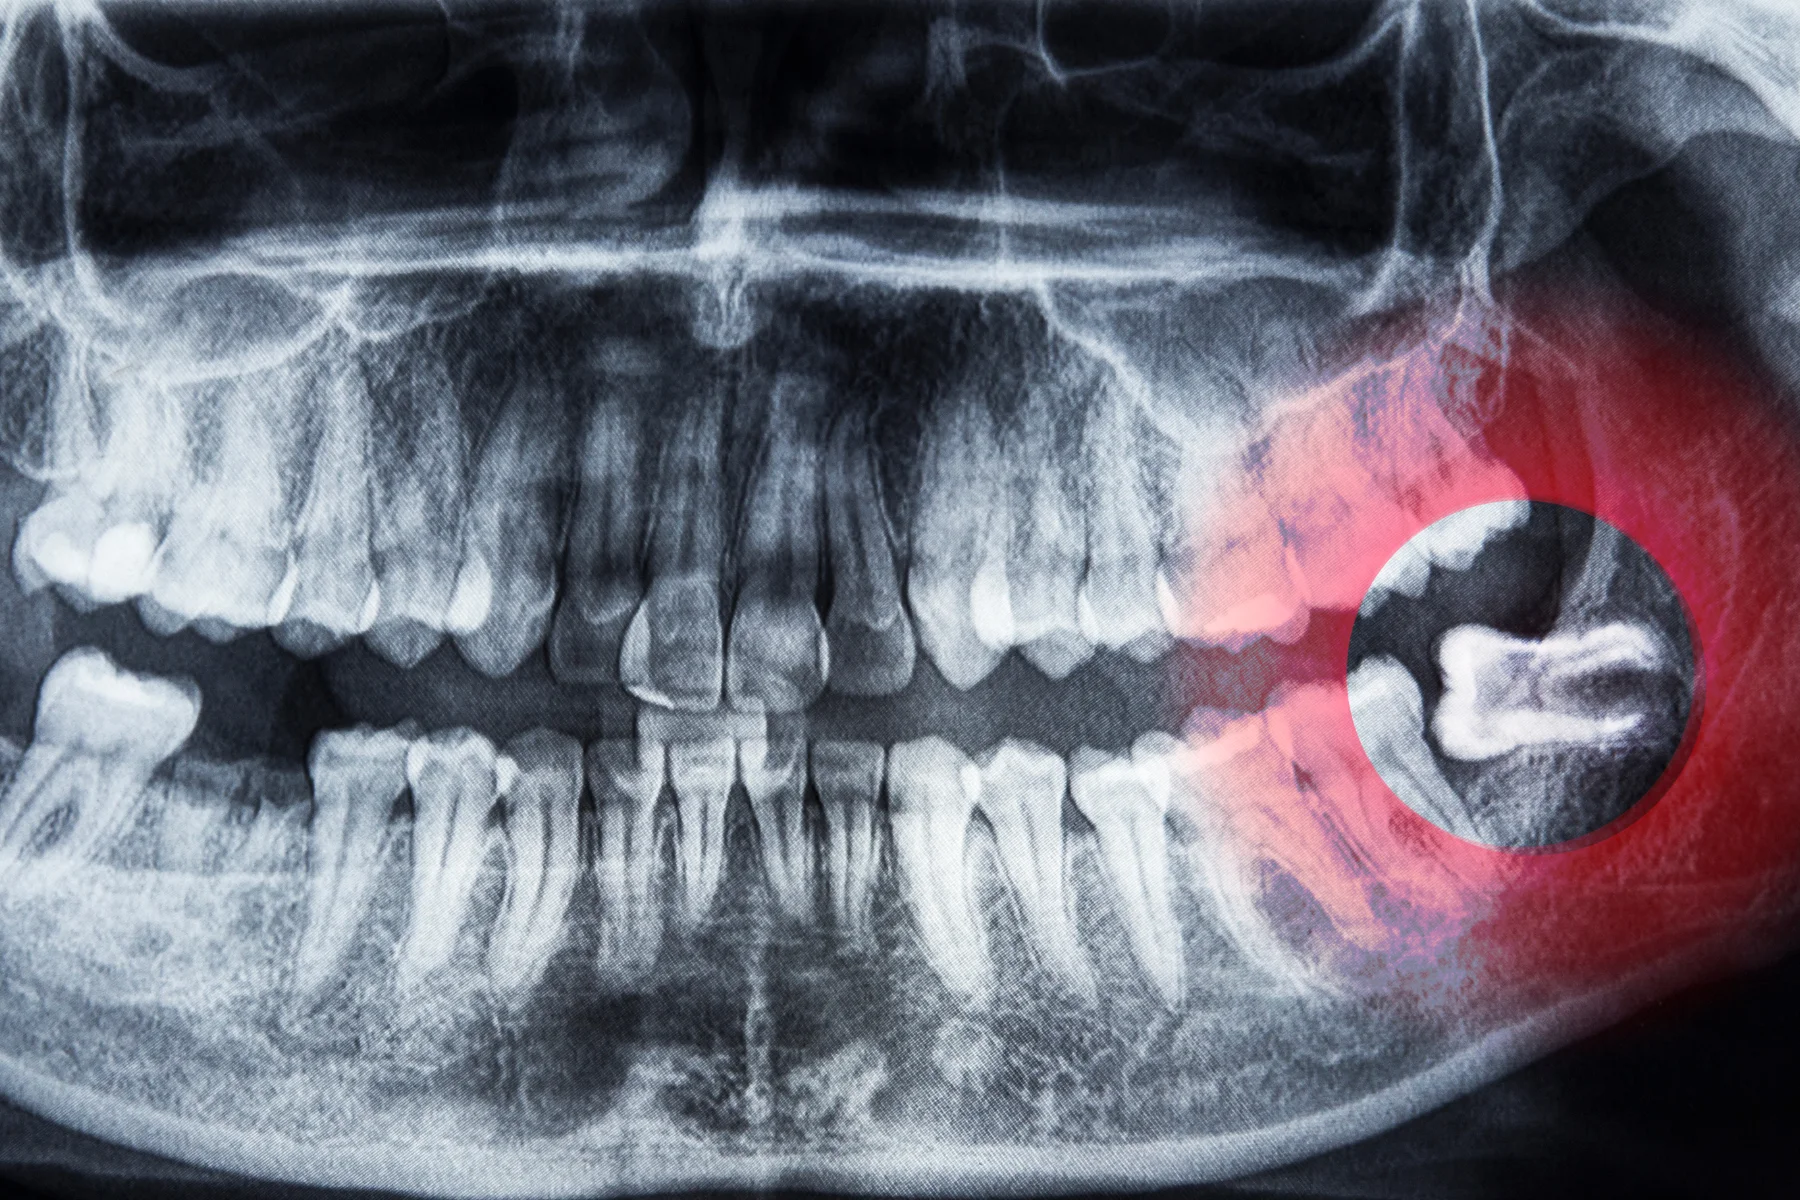

Wisdom tooth extraction, also called removal, is a surgical procedure to take out one or more wisdom teeth.

Many people have impacted wisdom teeth. These teeth don’t have enough room to appear in the mouth as usual.

An impacted wisdom tooth may:

• Grow at an angle toward the next tooth, the second molar.

• Grow at an angle toward the back of the mouth.

• Grow at a right angle to the other teeth, as if the wisdom tooth is “lying down” within the jawbone.

• Grow straight up or down like other teeth but stay trapped within the jawbone.

Wisdom teeth, also known as third molars, often need to be removed if they are impacted, misaligned, or causing problems such as pain, infection, or damage to adjacent teeth. Removing them can prevent future dental issues and discomfort.